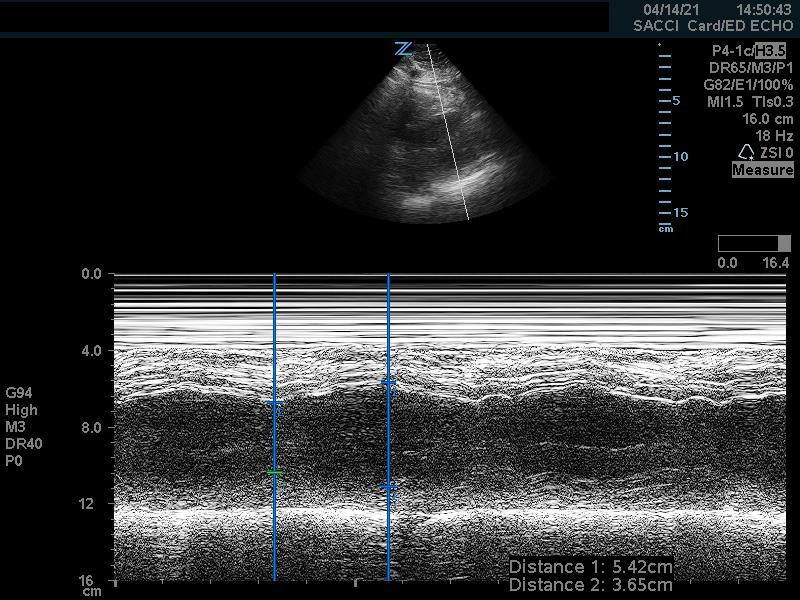

Fractional shortening can be used to estimate EF. This is performed by placing an M-mode spike through the anterior and posterior walls of the LV at the mid-LV in the parasternal short axis view. In M-mode, the diameter of the left ventricular cavity is measured in end-diastole (LVEDD) and end-systole (LVESD). One can then apply the below formula to obtain an estimation of EF%:

FS = (LVEDD-LVESD/LVEDD) x 100%

A normal EF is suggested by a percent FS between 25-45%. (Fig. 7,8)13

Figure 8. Parasternal short axis view at the mid-papillary level with fractional shortening measurement obtained using M-mode. Fractional shortening value of 19.6%, indicating hypodynamic LV systolic function.